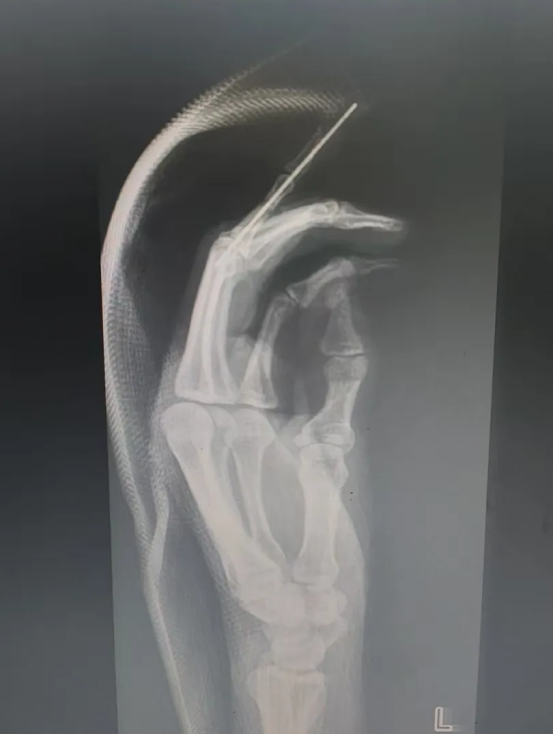

飞来横祸|机器绞伤,手指多段离断

吴女士(化名)在工作时不慎被机器绞伤左手,当即感到示指剧痛、出血并活动受限。家属迅速将其送至重庆郭昌毕中医骨伤医院急诊科。经检查并结合X光片,诊断为“左手示指多层面离断伤”,伴血管、神经、肌腱严重损伤,伤情复杂严峻。

术前摄片